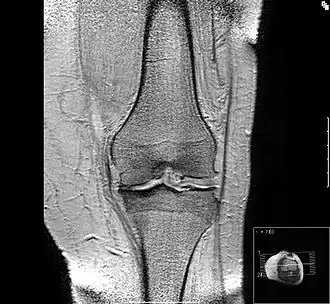

Исход артроза коленного и тазобедренного сустава

Исход артроза — полное разрушение сустава с формированием анкилоза — полной неподвижности сустава или неоартроза с неестественной подвижностью. Это сопровождается тяжёлым нарушением функции конечности. В последнее время, не дожидаясь исхода заболевания, всё чаще применяют специальные операции по замене сустава протезом — эндопротезирование сустава. На рисунке изображена типичная для терминальной стадии артроза коленного сустава варусная деформация колена в сочетании с боковой патологической нестабильностью коленного сустава. Артроз блоковидного или шаровидного сустава, такого как тазобедренный, завершается анкилозированием. При этом замыкание сустава обычно происходит в нефизиологическом (порочном) положении конечности. В данном случае мы видим бедро в положении сгибания и приведения, при котором нога укорачивается, а ось конечности и биомеханика опорно-двигательной системы существенно нарушается.